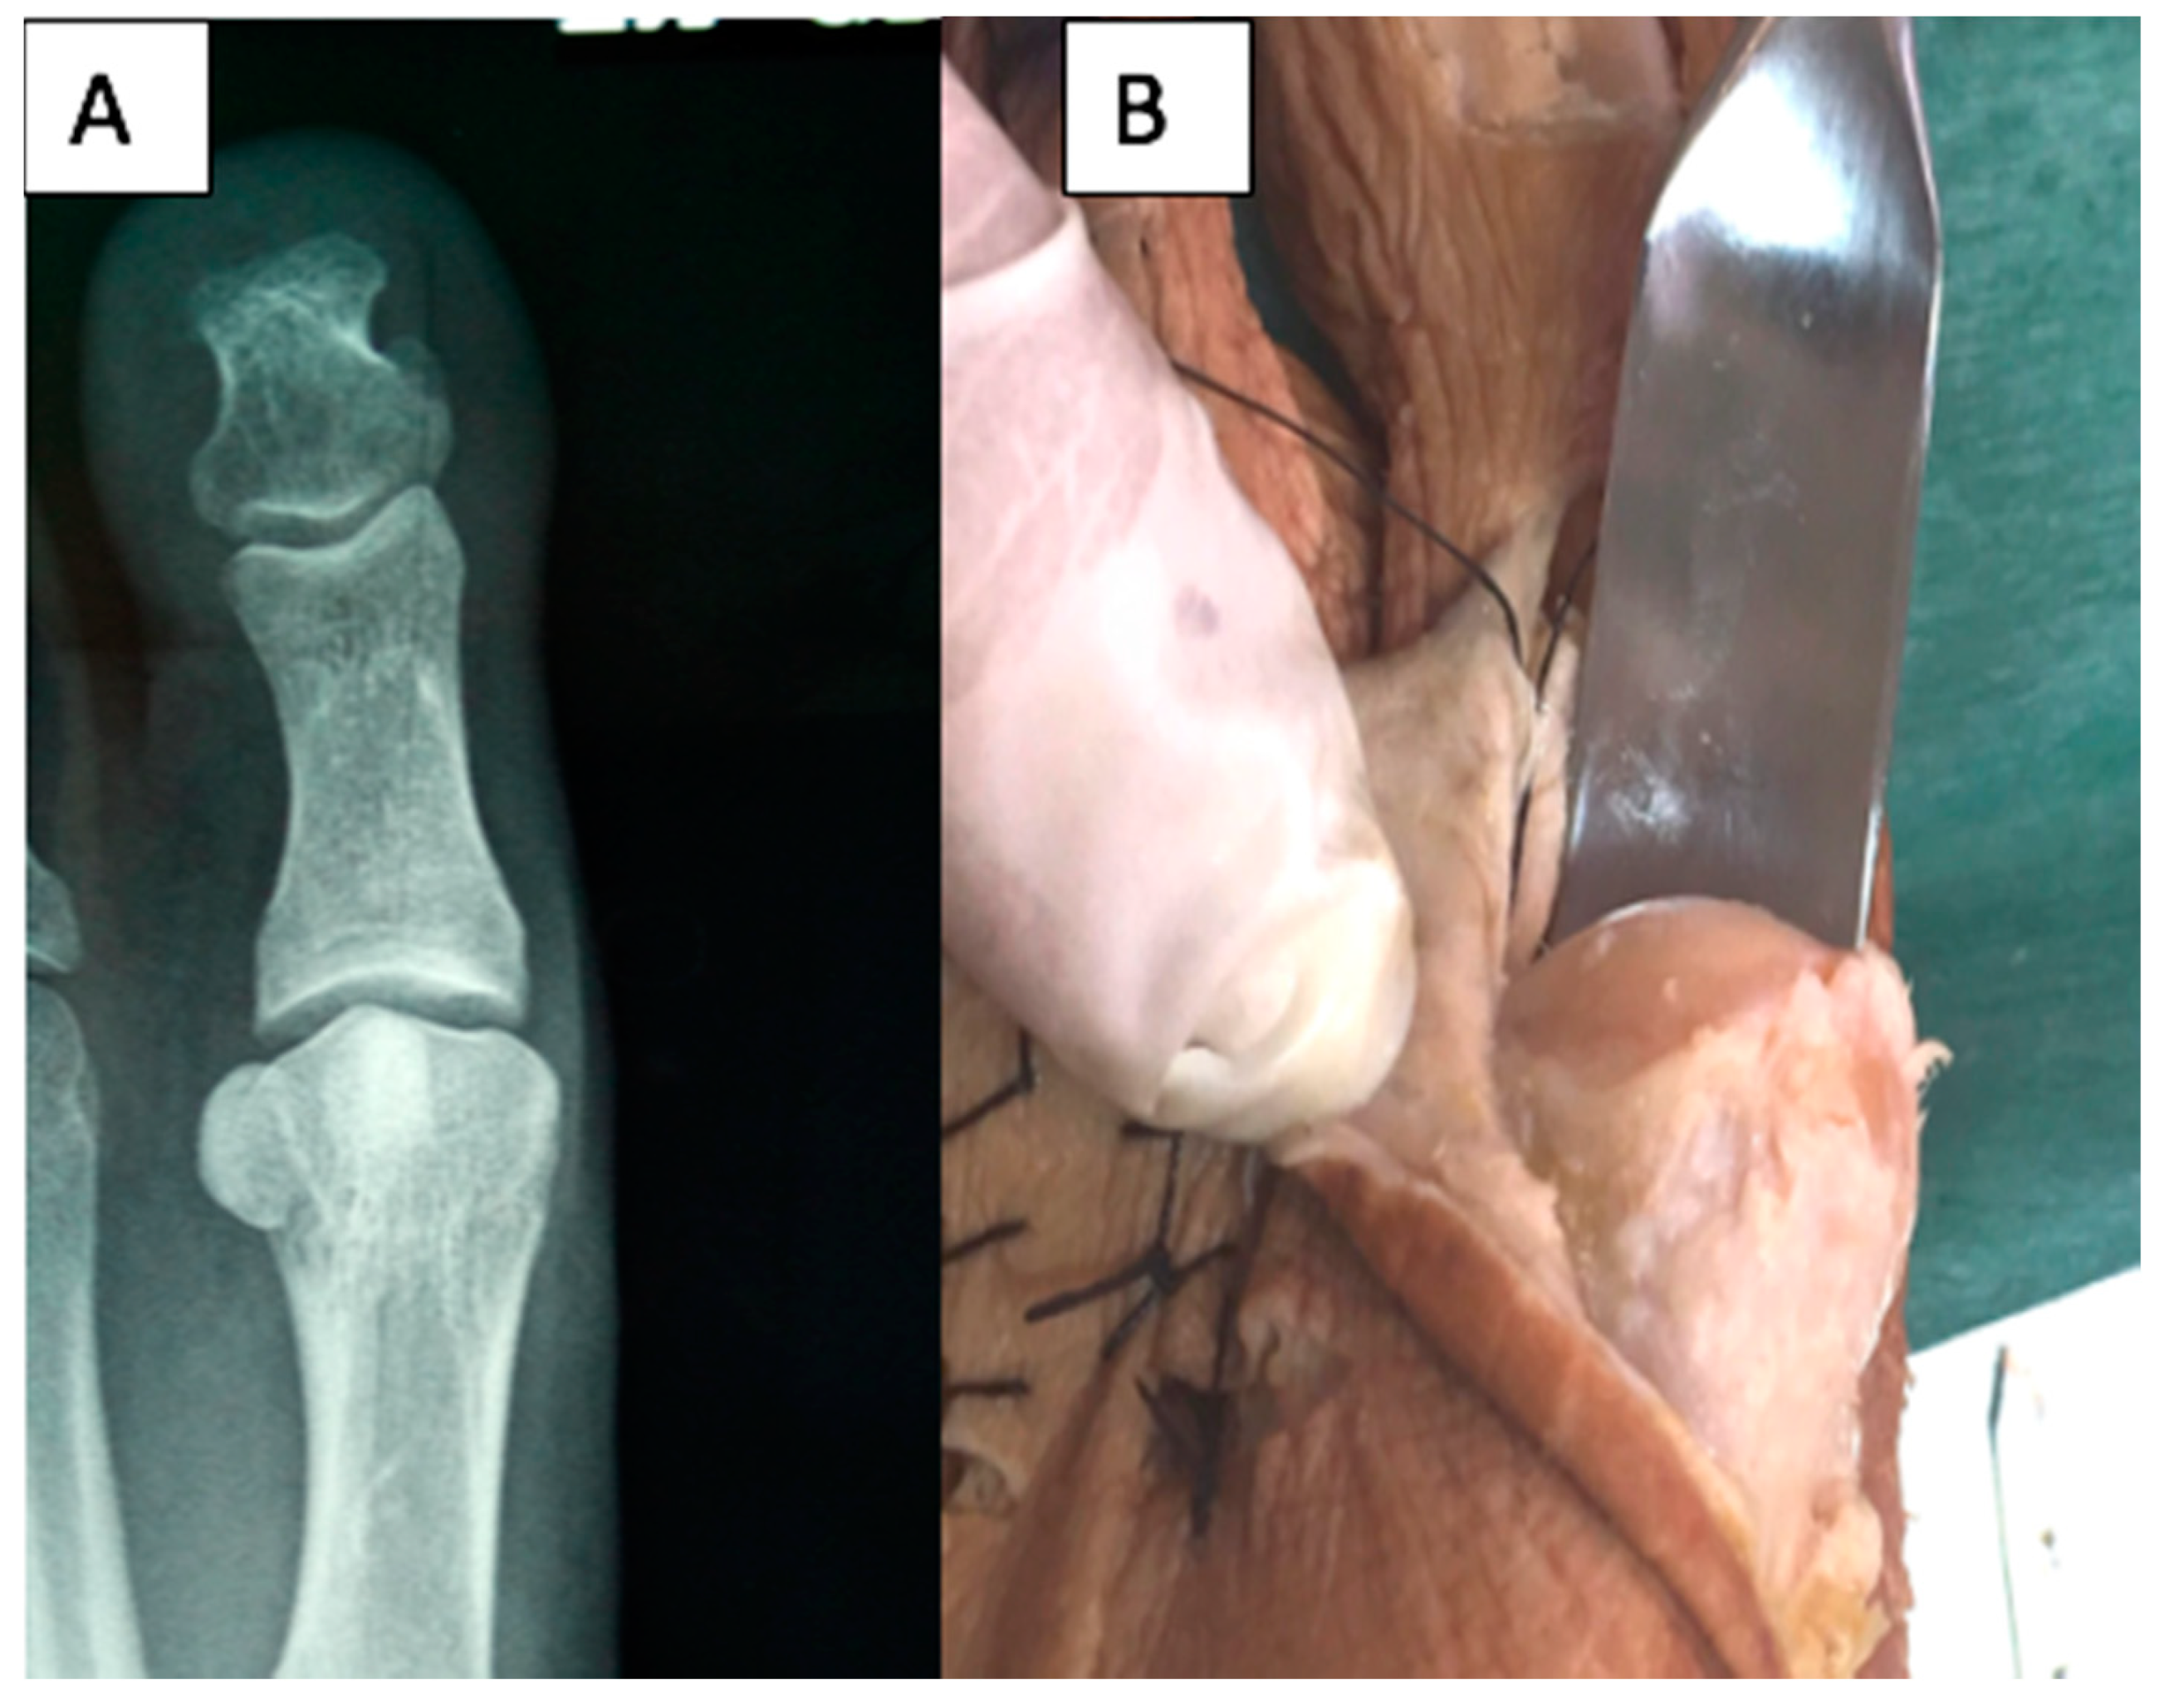

Both observers agree that the shape of the metatarsal head is distorted in projections in which the X-ray beam with angulations is equal to or greater than 20° (Figure 2).

Figure 2.

Views of a first metatarsal head showing distortion to appear crest shaped in a radiographic image performed to 30° (A) and after dissection revealing a round shape (B).